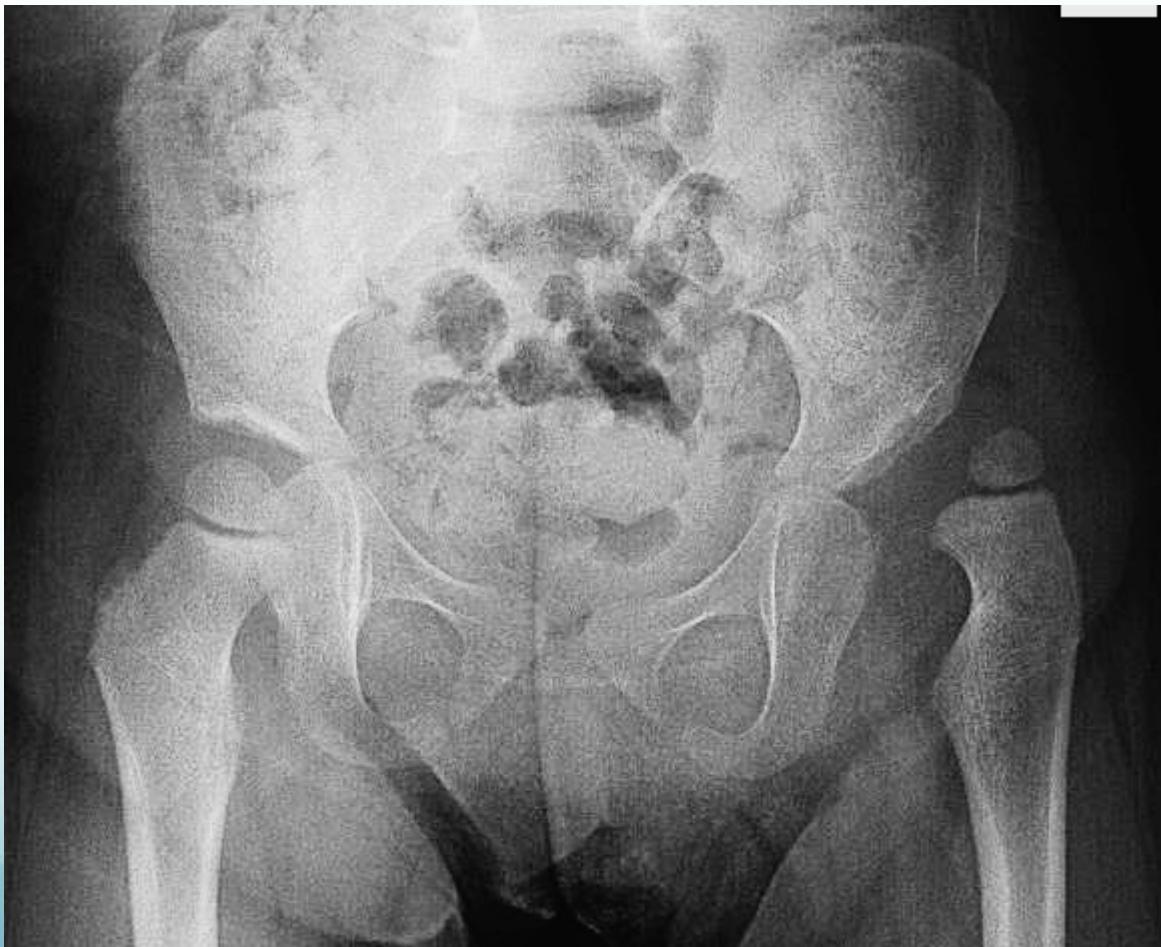

Above 2 years of age

- Surgery

- Open reduction & Acetabuloplasty & Femoral shortening

| 2-8 years | Open reduction, Acetabuloplasty, and femoral shortening |

| Above 8 years | Open reduction, Acetabuloplasty cutting all three pelvic bones, and femoral shortening |